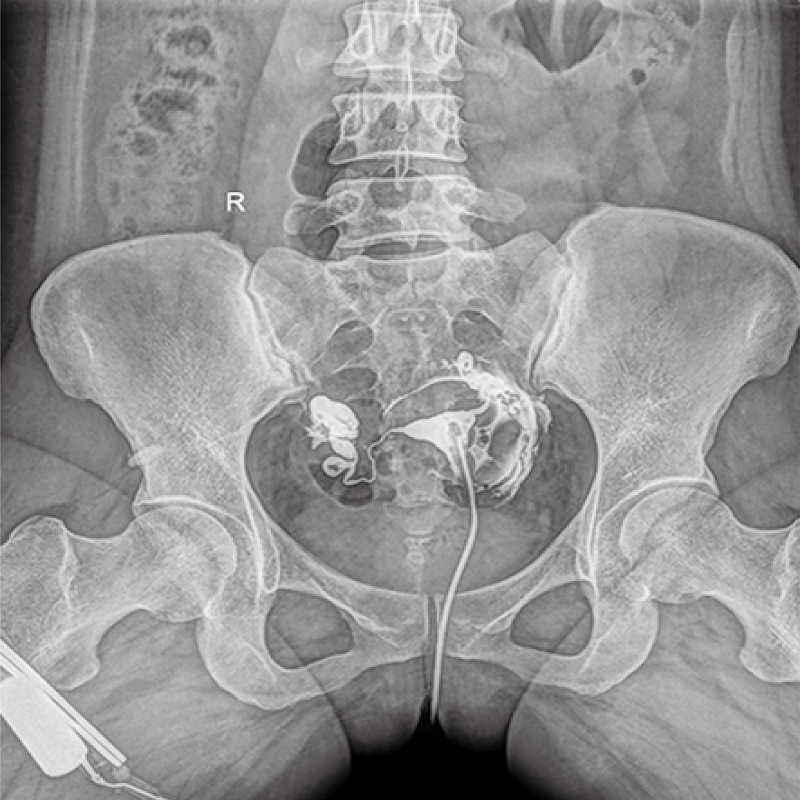

多功能、全視角、真視界,全面突破傳統(tǒng)X線攝影透視理念,通過(guò)一塊新型動(dòng)態(tài)平板探測(cè)器,在檢查中既可實(shí)現(xiàn)數(shù)字透視又可實(shí)現(xiàn)數(shù)字?jǐn)z影,還可做數(shù)字胃腸及數(shù)字造影檢查。

● 只需一塊動(dòng)態(tài)平板探測(cè)器,高效輕松實(shí)現(xiàn)攝影、透視和造影功能,幾乎可以滿足醫(yī)院全科室

● 大功率高頻高壓發(fā)生器,X射線硬度強(qiáng),穩(wěn)定性高,穿透性強(qiáng),輕松應(yīng)對(duì)體型肥胖的檢查者

● 原裝進(jìn)口大熱容量的高速X線管、雙焦點(diǎn)配置、持續(xù)工作時(shí)間更長(zhǎng),滿足大流量的臨床檢查需求